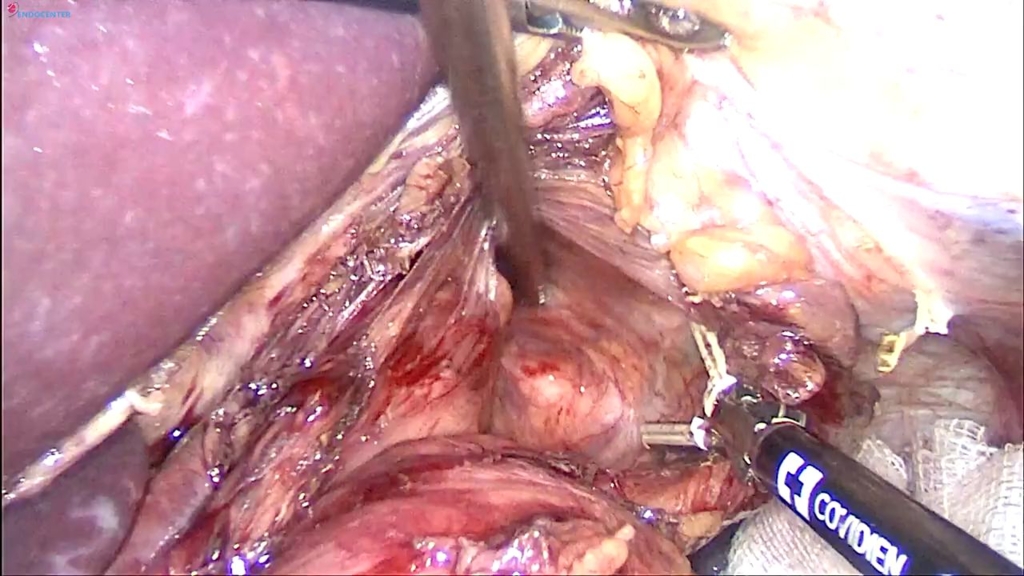

Laparoscopic oesophaeal diverticulus removal